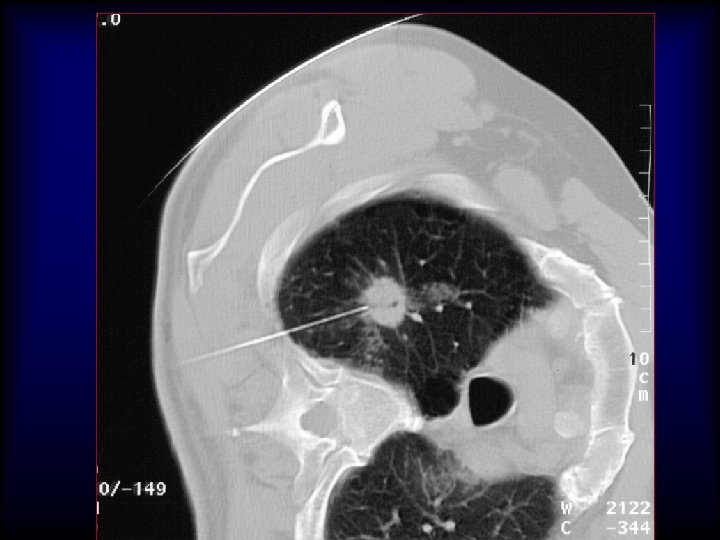

Lung nodule analysis • Evaluating Pulmonary Nodules Pulmonary nodules ≤ 4 mm have a low risk of being cancerous; • nodules between 4 -8 mm are of intermediate risk for cancer; follow up CT scans for both categories are recommended on different schedules • Pulmonary nodules >8 mm and mixed solid/ground glass nodules are suspicious for cancer; percutaneous needle aspiration biopsy (PNAB), positron emission tomography (PET), or video assisted thoracic surgery (VATS) should be considered

20 G/9 cm/10 T x 25 x 40 x 200 5 mm Adenocarcinoma H&E